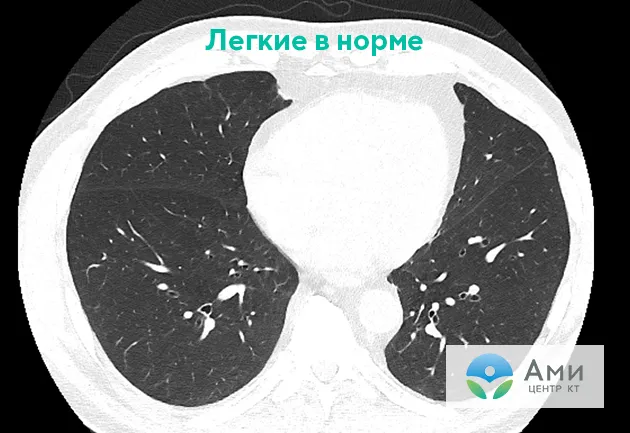

Повреждение легких на КТ при EVALI выглядит как пневмония. Оно определяется по симптомам «матового стекла» (очаги инфильтрации и уплотнения легочной ткани), локализованным в основном вокруг бронхов. Часто наблюдаются консолидация и затемнение. Чаще всего страдают нижнедолевые и субплевральные области легких — симметрично с обеих сторон.